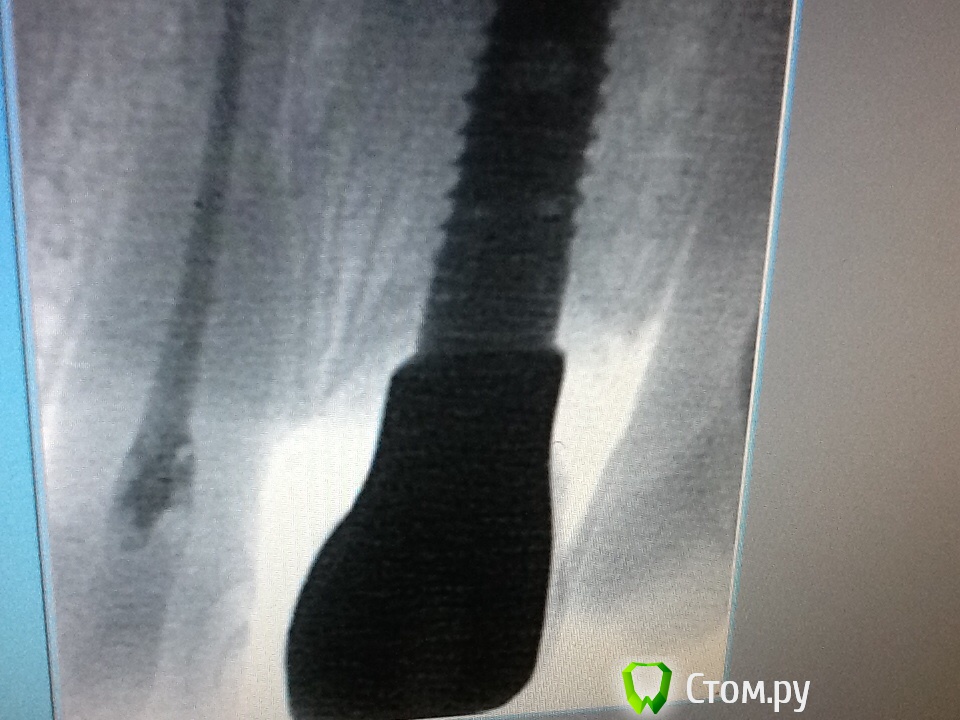

Военный Врач Опубликовано 10 апреля, 2014 Поделиться Опубликовано 10 апреля, 2014 (изменено) Коллеги, всем удачного дня! Делаю первую процеру на Нобеле. Сегодня пришла коронка- сделал рг-это нормально что платформа так выпирает-как ступенька или я придираюсь? Изменено 10 апреля, 2014 пользователем Военный Врач 1 Ссылка на комментарий

vesvova Опубликовано 10 апреля, 2014 Поделиться Опубликовано 10 апреля, 2014 Возможно вы за ступеньку приняли поддесневую часть абатмента! Ссылка на комментарий

PLAY Опубликовано 11 апреля, 2014 Поделиться Опубликовано 11 апреля, 2014 та по идее не должно быть так. индивидуальный абатмент в месте соединения с платформой имплантата должен быть уже, ну или хотя бы вровень 1 Ссылка на комментарий

r3yand Опубликовано 11 апреля, 2014 Поделиться Опубликовано 11 апреля, 2014 Это похоже на какой-то обратный платформ-свитч... странно как-то выглядит, честно говоря)Ждем главных нобелистов) Ссылка на комментарий

Военный Врач Опубликовано 11 апреля, 2014 Автор Поделиться Опубликовано 11 апреля, 2014 Это похоже на какой-то обратный платформ-свитч... странно как-то выглядит, честно говоря)Ждем главных нобелистов)так ведь вот.. что делать-то? заставить переточить или все ок? Ссылка на комментарий